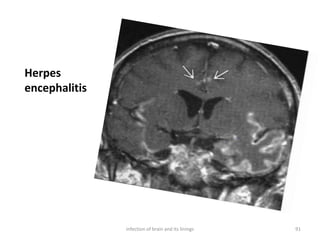

Herpes

encephalitis

91infection of brain and its linings